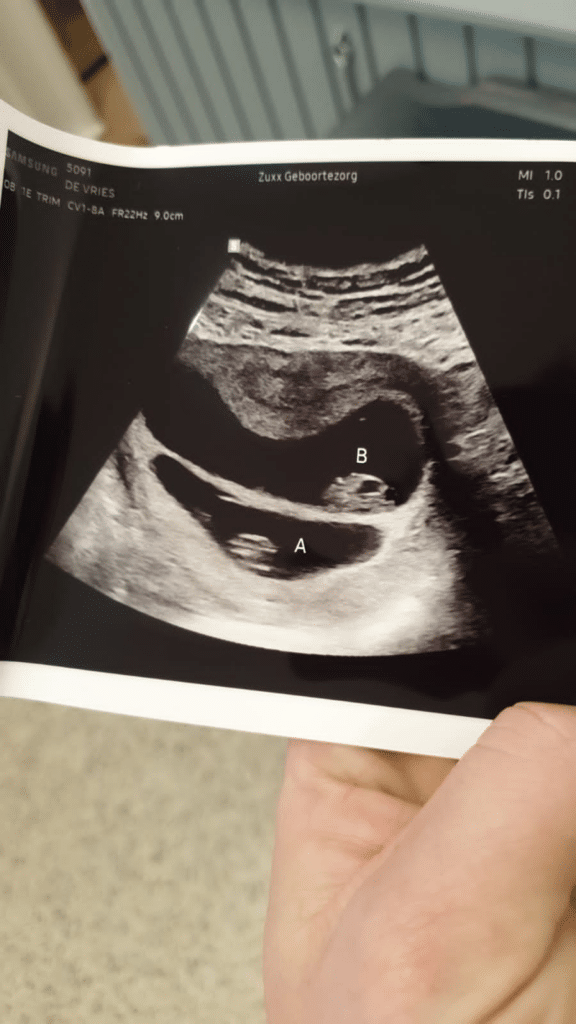

Als ik eenmaal goed en wel op de stoel lig en mijn partner op het bankje ernaast legt ze uit wat ze gaat doen en waar de echo voor is. Ze noemt een aantal dingen op onderwijl ze alles gereed maakt en de gel op mijn buik spuit, ze gaat kijken of het op de goede plek zit, of het hartje klopt, hoever ik ben en een beetje lachend zegt ze ‘en even kijken hoeveel het er zijn’. Hierop reageert mijn partner direct met ‘vooral dat het er 1 is is belangrijk’. Exact op het moment dat hij op de verloskundige reageert zet ze het echo apparaat op mijn buik en ik zie het meteen.. Ik geloof dat de verloskundige een beetje schrok en het ook direct zag want ze haalt meteen het apparaat van mijn buik, neemt een zucht en zet hem er weer op om meteen te zeggen ‘Ik kan je meteen uit de droom helpen, gefeliciteerd het zijn er twee’.

Er zitten twee baby’s in mijn buik met prachtige kloppende hartjes en ik ben iets meer dan 8 weken zwanger. OH MIJN GOD! Ik kan het haast niet geloven..